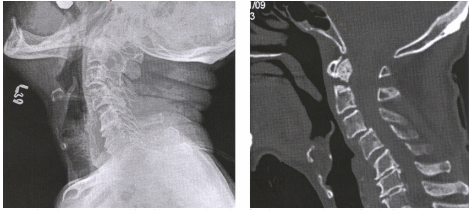

74 一位 79 歲男性,下列左圖為其側面頸椎 X 光片,右圖為其電腦斷層矢狀面重組之頸椎影像,其第一 及第二頸椎病變之敘述,以何者為最正確?

(A) C1-C2 subluxation (B) odontoid fracture with non-united gap (C) infection of odontoid process (D) metastatic bone lesion of C2